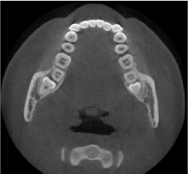

歯科用CT検査

■歯科用CTとは

歯科用CT(Computed Tomography)は、CT撮影装置とコンピュータ処理により、歯科領域における撮影データを3次元的に構築し、骨の状態などが正確・高精度に診断できる装置です。通常のCTよりも高解像度なので歯や骨等を詳細にみることができます。また、歯科用CTはインプラント治療だけでなく、矯正や根管治療、親知らずなど、幅広く様々な歯科治療の支援に用いられます。

■当院の装置

AUGE SOLIO(朝日レントゲン社)